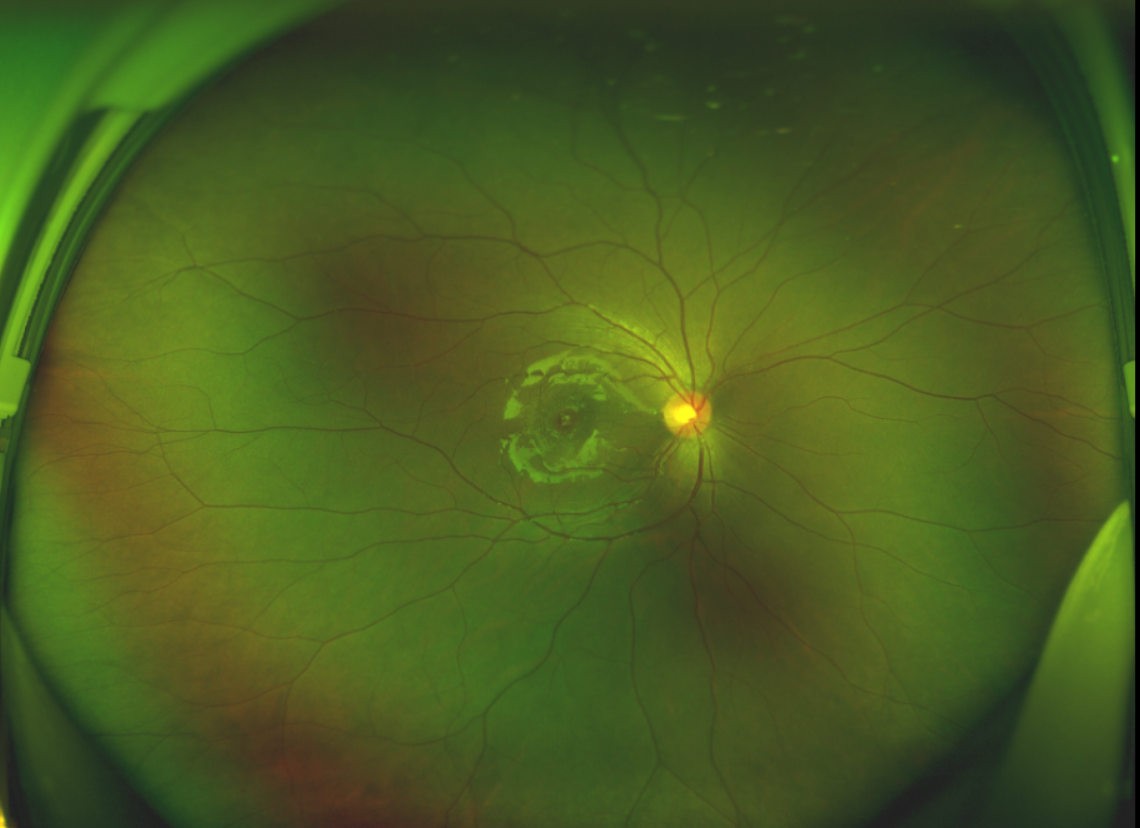

半年前的一次意外,誠誠(化名)右眼不慎受傷導(dǎo)致黃斑裂孔。從此,他的“視”界不再清晰,也不再有直線條……

黃斑位于視網(wǎng)膜正中心,是視覺最敏銳的區(qū)域,堪稱“眼底的心臟”,負責(zé)我們閱讀、駕駛、識別人臉等精細視覺。 當(dāng)黃斑區(qū)的神經(jīng)組織出現(xiàn)全層缺損,形成一個“孔洞”,即為黃斑裂孔,它會直接導(dǎo)致中心視力急劇下降、視物變形、視野中心出現(xiàn)暗區(qū)。

除此之外,利用自體組織覆蓋為黃斑裂孔提供了理想的愈合環(huán)境,裂孔閉合速度顯著快于傳統(tǒng)方法。誠誠接受手術(shù)24小時后,檢查可見內(nèi)界膜瓣位置良好;術(shù)后1個月,黃斑裂孔已經(jīng)閉合,視力恢復(fù)到0.5;術(shù)后兩個月,視力進一步提升到0.7。